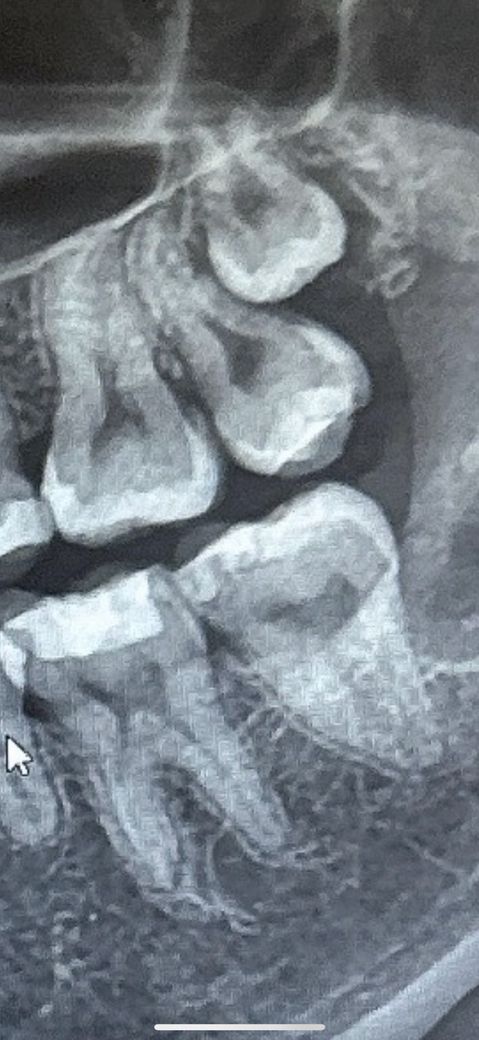

6-7번 치아 사이에 인접면 충치가 있는걸로 보여지나요??

6-7번 치아 사이에 충치가 있는걸로 보여질까요??

하악6-7번 사이에 치실이 잘 안 들어가는 느낌(반대쪽은 치실이 잘 들어가지니다) 에다가

육안 관찰 시에 갈색으로 충치가 시작되려는 단계인지 초기 충치인지 관찰이 되었는데 궁금합니다

앞 치아는 인레이 치료가 되어있긴한데요

6~7번 사이에는 인접면 충치가 있는 것처럼 보이기도 합니다. 하지만 정확한 확인을 위해서는 육안으로 확인을 해야 합니다. 인레이나 레진 등으로 광범위하게 치아를 수복한 치아에 인접면에 충치가 생겼다면 크라운 치료를 하는 것이 좋을 수 있습니다.

엑스레이 정도라면 충치치료를 하지 않으셔도 되고 치실로 관리만 하셔도 충분할것같습니다.

사진을 치근단으로 찍어서 올려주시면 더 정확합니다. 치료가 필요한 정도로 보이는 것 같습니다.

인접면 충치는 있는 것으로 방사선 사진상 보이고, 저정도면 레진보다는 인레이로 할 것 같습니다.